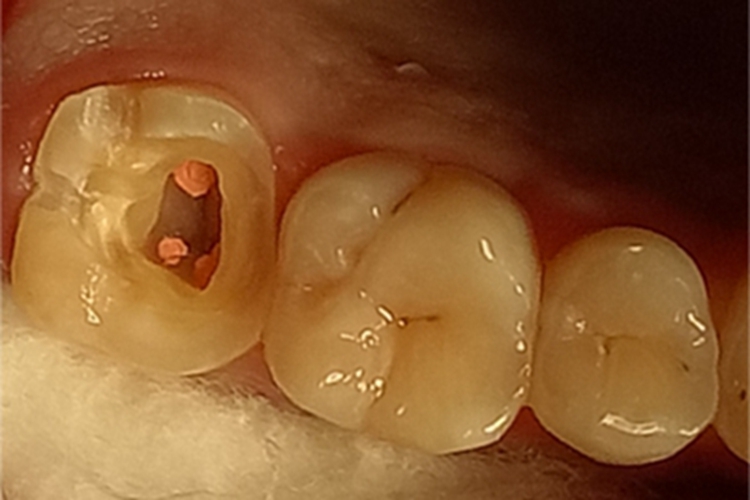

死髓牙患者一般没有自觉症状,仅以牙冠变色为主诉前来就诊。临床检查可以发现患牙牙冠存在深龋洞或是牙冠有重度的磨耗,牙冠变色,呈暗黄色或灰色,失去光泽;有穿髓孔的患牙,探查穿髓孔无反应。